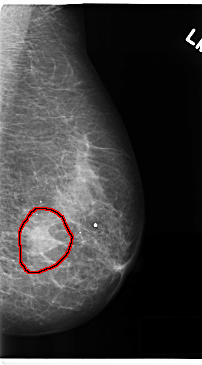

C_0216_1.LEFT_CC

LEFT_CC LINES 4760 PIXELS_PER_LINE 2632 BITS_PER_PIXEL 12 RESOLUTION 50 OVERLAY

FILE: C_0216_1.LEFT_CC.OVERLAY

TOTAL_ABNORMALITIES 1

ABNORMALITY 1

LESION_TYPE MASS SHAPE IRREGULAR MARGINS ILL_DEFINED

ASSESSMENT 5

SUBTLETY 5

PATHOLOGY MALIGNANT

TOTAL_OUTLINES 1

BOUNDARY